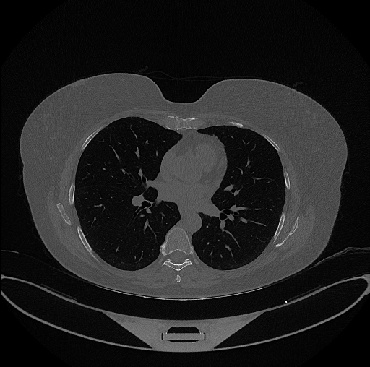

Figure 1 shows four CT scan slices, two from a non-COVID-19 CT scan, on the left and two from a COVID-19 scan, on the right. Bilateral ground glass regions are seen especially in lower lung lobes in the COVID-19 slices.